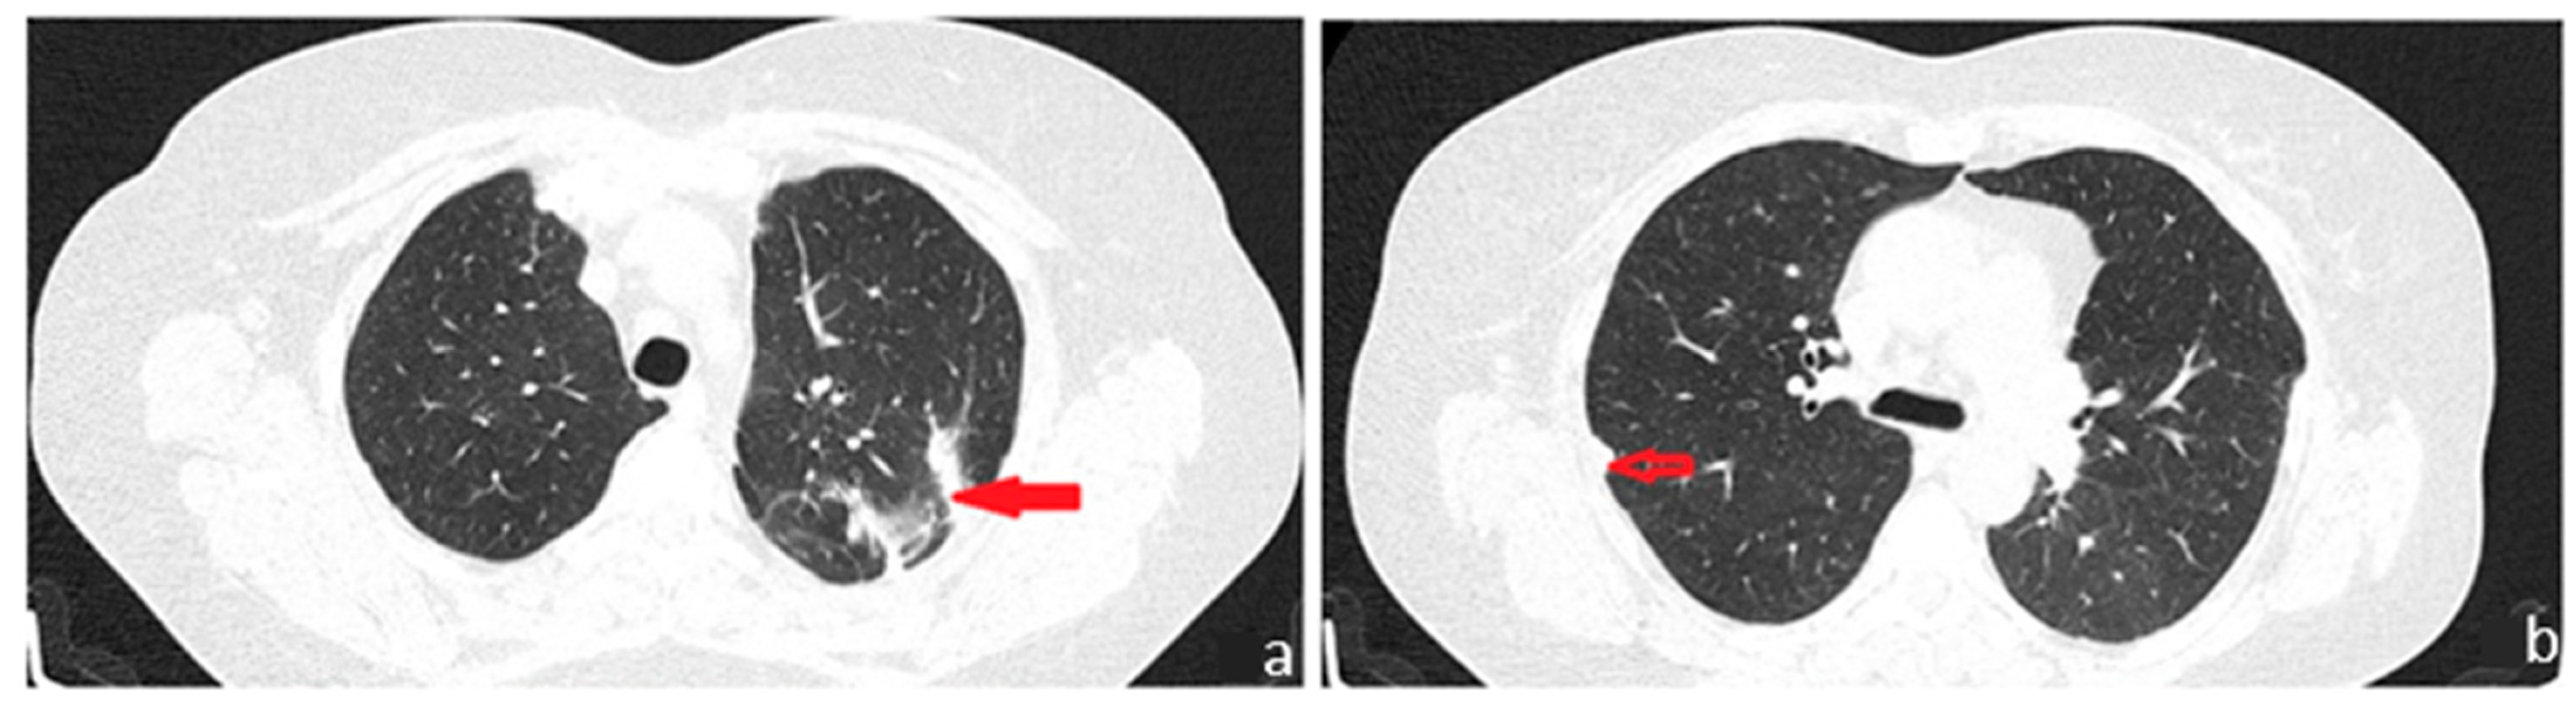

Figure 4. During the patient’s follow-up six months later, she was found to be in good general condition, with minimal respiratory symptoms and a chest CT imaging assessment with no particularities. We believe that the interstitial changes detected in the initial chest CT examination most likely represent the residual signs of an infection that was suppressed while undergoing broad-spectrum antibiotic treatment and symptomatic care, as initially recommended during the initial medical evaluation in the field. Right apical sequelae fibrotic changes ((a): red arrow) were observed, consistent with the findings before the surgical intervention, as well as residual postoperative changes ((b): red transparent arrow) located in the left subpleural area. Moreover, there was a regression of the ground glass imaging appearance, which was present bilateral, in bases, in March 2023. Thus, the lack of respiratory symptoms and the absence of progression in the imaging lesions represented the arguments for the localized substrate of the condition. Subsequently, immunohistochemistry tests were performed, which confirmed the diagnosis. Although the histopathological diagnosis of pulmonary amyloidoma was established, a comprehensive spectrum of investigations was conducted to exclude systemic damage. The presence of the nonspecific inflammatory syndrome with a high level of CRP and the increased serum titer of amyloid A dictated investigations in search of a secondary amyloidotic substrate. Complementary to the histopathological examination, the performance of immunohistochemistry (IHC) tests, bone marrow biopsy, abdominal fat pad biopsy, and salivary gland biopsies would have been useful during the diagnosis process in order to evaluate systemic lymphoproliferative disorders and plasma cell dyscrasias, but the decision to not undergo all these procedures and the timing of their performance was the patient’s decision. At this moment, the absence of disease progression most likely denotes the indolent character of the disease but does not ensure its benignity and possible distant involvement. The approach chosen is to closely monitor the case, with the patient undergoing periodic interdisciplinary consultations. The current case outlines the diagnostic process for the pulmonary nodular amyloidoma, a rare disorder with only 12 cases reported in the literature [1], established secondary to an exhaustive panel of investigations, triggered by the radiological discovery of a pulmonary nodule. The initial imaging appearance with the nodular mass in the left upper lobe, associated with other discrete interstitial changes in the lower lung areas, bilaterally, imposed a laborious differential diagnosis. Additional hypotheses included fungal infections, benign nodules of various etiologies, neoplastic substrate, or, given that our country remains endemic for tuberculosis, a bacillary etiology. Similar to other reported cases, excisional surgical biopsy was mandatory, as the ‘gold standard’ for diagnosis continues to be the histopathological examination, which demonstrates apple-green birefringence with polarized microscopy after staining with Congo red [2]. The particularity of the case lies in the earliness of the diagnosis, given that the disease was detected in this limited form, with the absence of signs of systemic involvement, although it is not excluded that it may evolve into multi-organ impairment in the future.